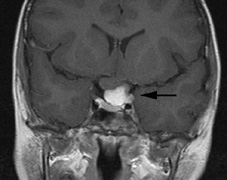

Optic nerve gliomas may involve the optic chiasm and be associated with endocrine disorders or nystagmus.68–70 Surgical excision of chiasmal gliomas (Fig. 6) carries a high risk of visual loss. Invasion of the hypothalamus or the third ventricle carries a poor prognosis, with greater than 50% 15-year mortality rate.71 One review of radiation treatment for chiasmal gliomas collated data from small case series and found no significant long-term improvement in visual function, progression, or mortality with radiation treatment.71 Other reports suggest that radiation doses over 4500cGy improve symptoms and slow progression of chiasmal gliomas over several years.72 Adequate tumor coverage by radiotherapy results in irradiation of normal brain and nearly all children need hormone replacement.73 Chemotherapy is an alternative.74,75

Fig. 6. Surveillance images of a 12-year-old girl with NF1 and an optic nerve glioma which has extended to involve the chiasm. Pre- (a) and postcontrast (b) T1-weighted coronal images reveal a large suprasellar mass with an enhancing component (arrow) seen separately from the normally enhancing pituitary gland. (c) Axial scans through the suprasellar cistern show the tumor is high signal on T2-weighted scans. (d) Enlargement of the chiasm, optic nerve and hypothalamus is visible on the post-contrast T1-weighted sagittal image. Although optic nerve glioma usually has a good prognosis (with visual function often remaining stable in the absence of any intervention66,67), chiasmal involvment is a poor prognostic indicator. A sign of chiasmal involvment may be new onset of endocrine disorders or nystagmus. Surgical excision of chiasmal gliomas carries a high risk of visual loss.68–70